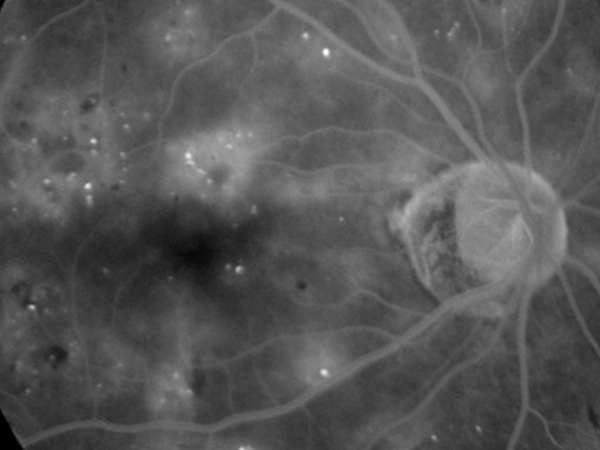

Fluorangiografia retinica

La fluorangiografia è un esame fondamentale per lo studio della retina. Si esegue iniettando in vena un mezzo di contrasto e scattando poi delle foto con uno strumento specifico.

Nelle forme di uvette posteriore è indispensabile per individuare le aree retiniche maggiormente affette dalla patologa infiammatoria.